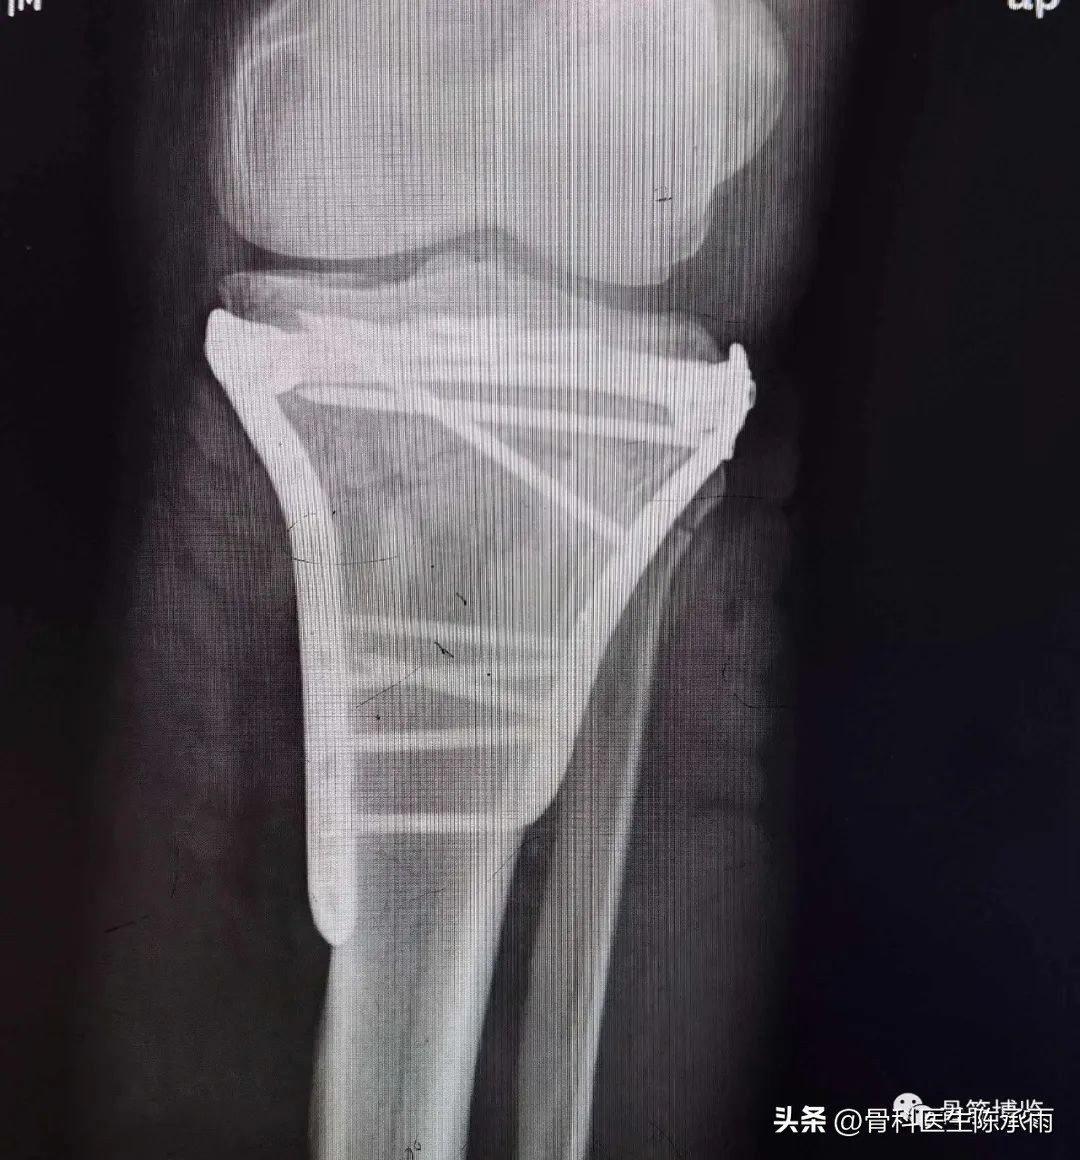

胫骨平台骨折的分型比较多,我们临床上常用的就是Schatzker分型和AO骨折的分型,还有骨折脱位的Hohi-Moore分型,这是我们常用的三个分型。

Schatzker分型来讲它一共分为六型:

一型 劈裂,

二型 劈裂塌陷,

三型 外髁的一个单纯塌陷,

四型 内髁的骨折,

五型 双髁的骨折,

六型 双髁伴干骺端的骨折,

对AO 分型来讲,现在这是AO推出来更详细的,再分为ABC。随着分型的增加,从A到C骨折的损伤程度是越来越重,治疗也越来越困难,从1到2 ,123也是这个规律,骨折的分型就是给我们表明了骨折的一个损伤的程度,治疗办法和损伤的特点。我们对于骨折脱位的分型,常用Hohi-Moore分型,这个是弥补了,Schatzker和AO分型的一些缺陷。

1例

2例

3例

4例

5例

6例

7例